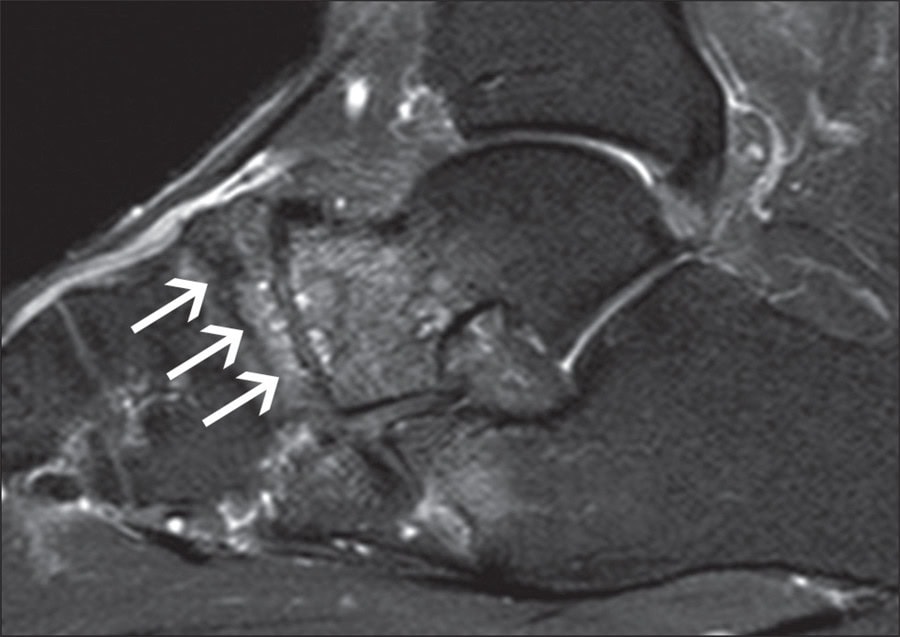

O diagnóstico é baseado na combinação de achados clínicos e de imagem. A radiografia simples geralmente mostra esclerose, fragmentação e colapso do osso navicular. A ressonância magnética é o exame mais sensível, demonstrando alterações precoces da necrose avascular antes das alterações radiográficas evidentes.

O acompanhamento regular com exames de imagem seriados é importante para monitorar a progressão da doença e ajustar o plano terapêutico. A ressonância magnética é particularmente útil para avaliar a viabilidade óssea residual e guiar decisões sobre a intensidade do tratamento.